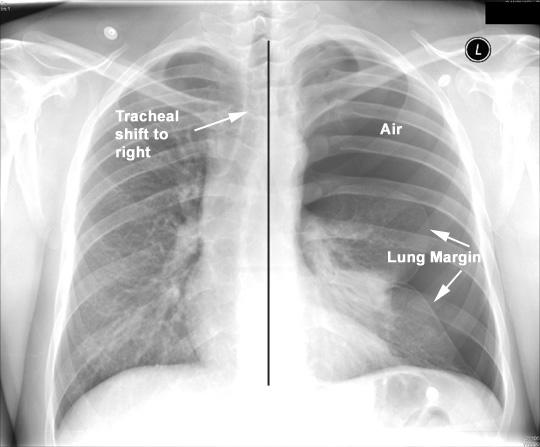

Pneumothorax

• Air in the pleural cavity

• No vascular markings

• Dark

• Atelectatic lung margin

• Shift of Mediastinum to opposite side

• Left hemithorax larger, closer to TLC position